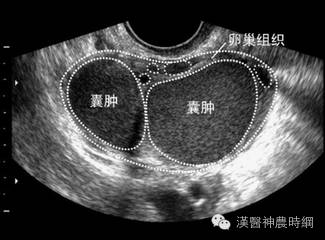

B超声象图:B超显象是目前辅助诊断子宫内膜异位症的有效方法,主要用以观察卵巢子宫内膜异位囊肿,其声象图的特征为:囊性肿块,边界清晰或不清。如囊肿周围粘连重,则边界不清;如囊肿与子宫或周围组织粘连少,则边界清晰。囊肿多为中等大小,囊肿内可见颗粒状细小回声,是囊液粘稠表现。有时因陈旧性血块浓缩机化而出现较密集的粗光点图象,呈混合性肿块状。

肿块常位于子宫后侧,可见囊肿子宫伴随症。囊肿自发破裂时,声象图示后凹陷,囊肿较前缩小。腹腔镜检查:腹腔镜检查是目前诊断子宫内膜异位症的新标准,通过腹腔镜可直接窥视盆腔,见到异位病灶即可明确诊断,且可进行临床分期,以决定治疗方案。